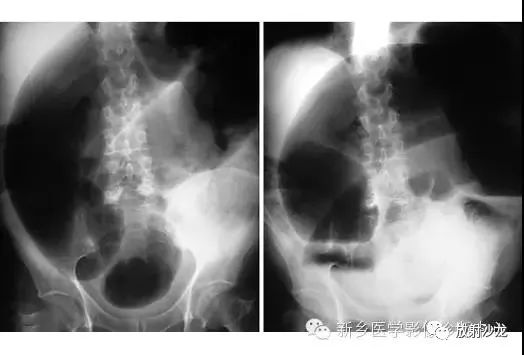

腹痛患者的腹部X光片水平位(左侧)和直立位(右侧)所上图示。是什么原因导致该病人的不适呢?

X线片表现出充满整个腹部的乙状结肠扭转。乙状结肠的两端可以理解成一个倒置的朝向骨盆的U型(图U)。在X光片直立位,可以看出气液平面(箭头)。咖啡豆的标志是乙状结肠扭转的典型的表现。充满气体的肠道包绕重叠水肿的肠壁所形成致密的白线,类似于一个咖啡豆。在这些X光片中,大肠的其余部分均不膨大,大概是因为扭转的点不造成阻塞,从而使消化产物可进入乙状结肠。

逆行通过肛管后所行X光片所示,证明了乙状结肠襻和正常肠道结构压力减低。